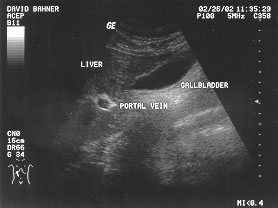

Gallbladder (labeled)